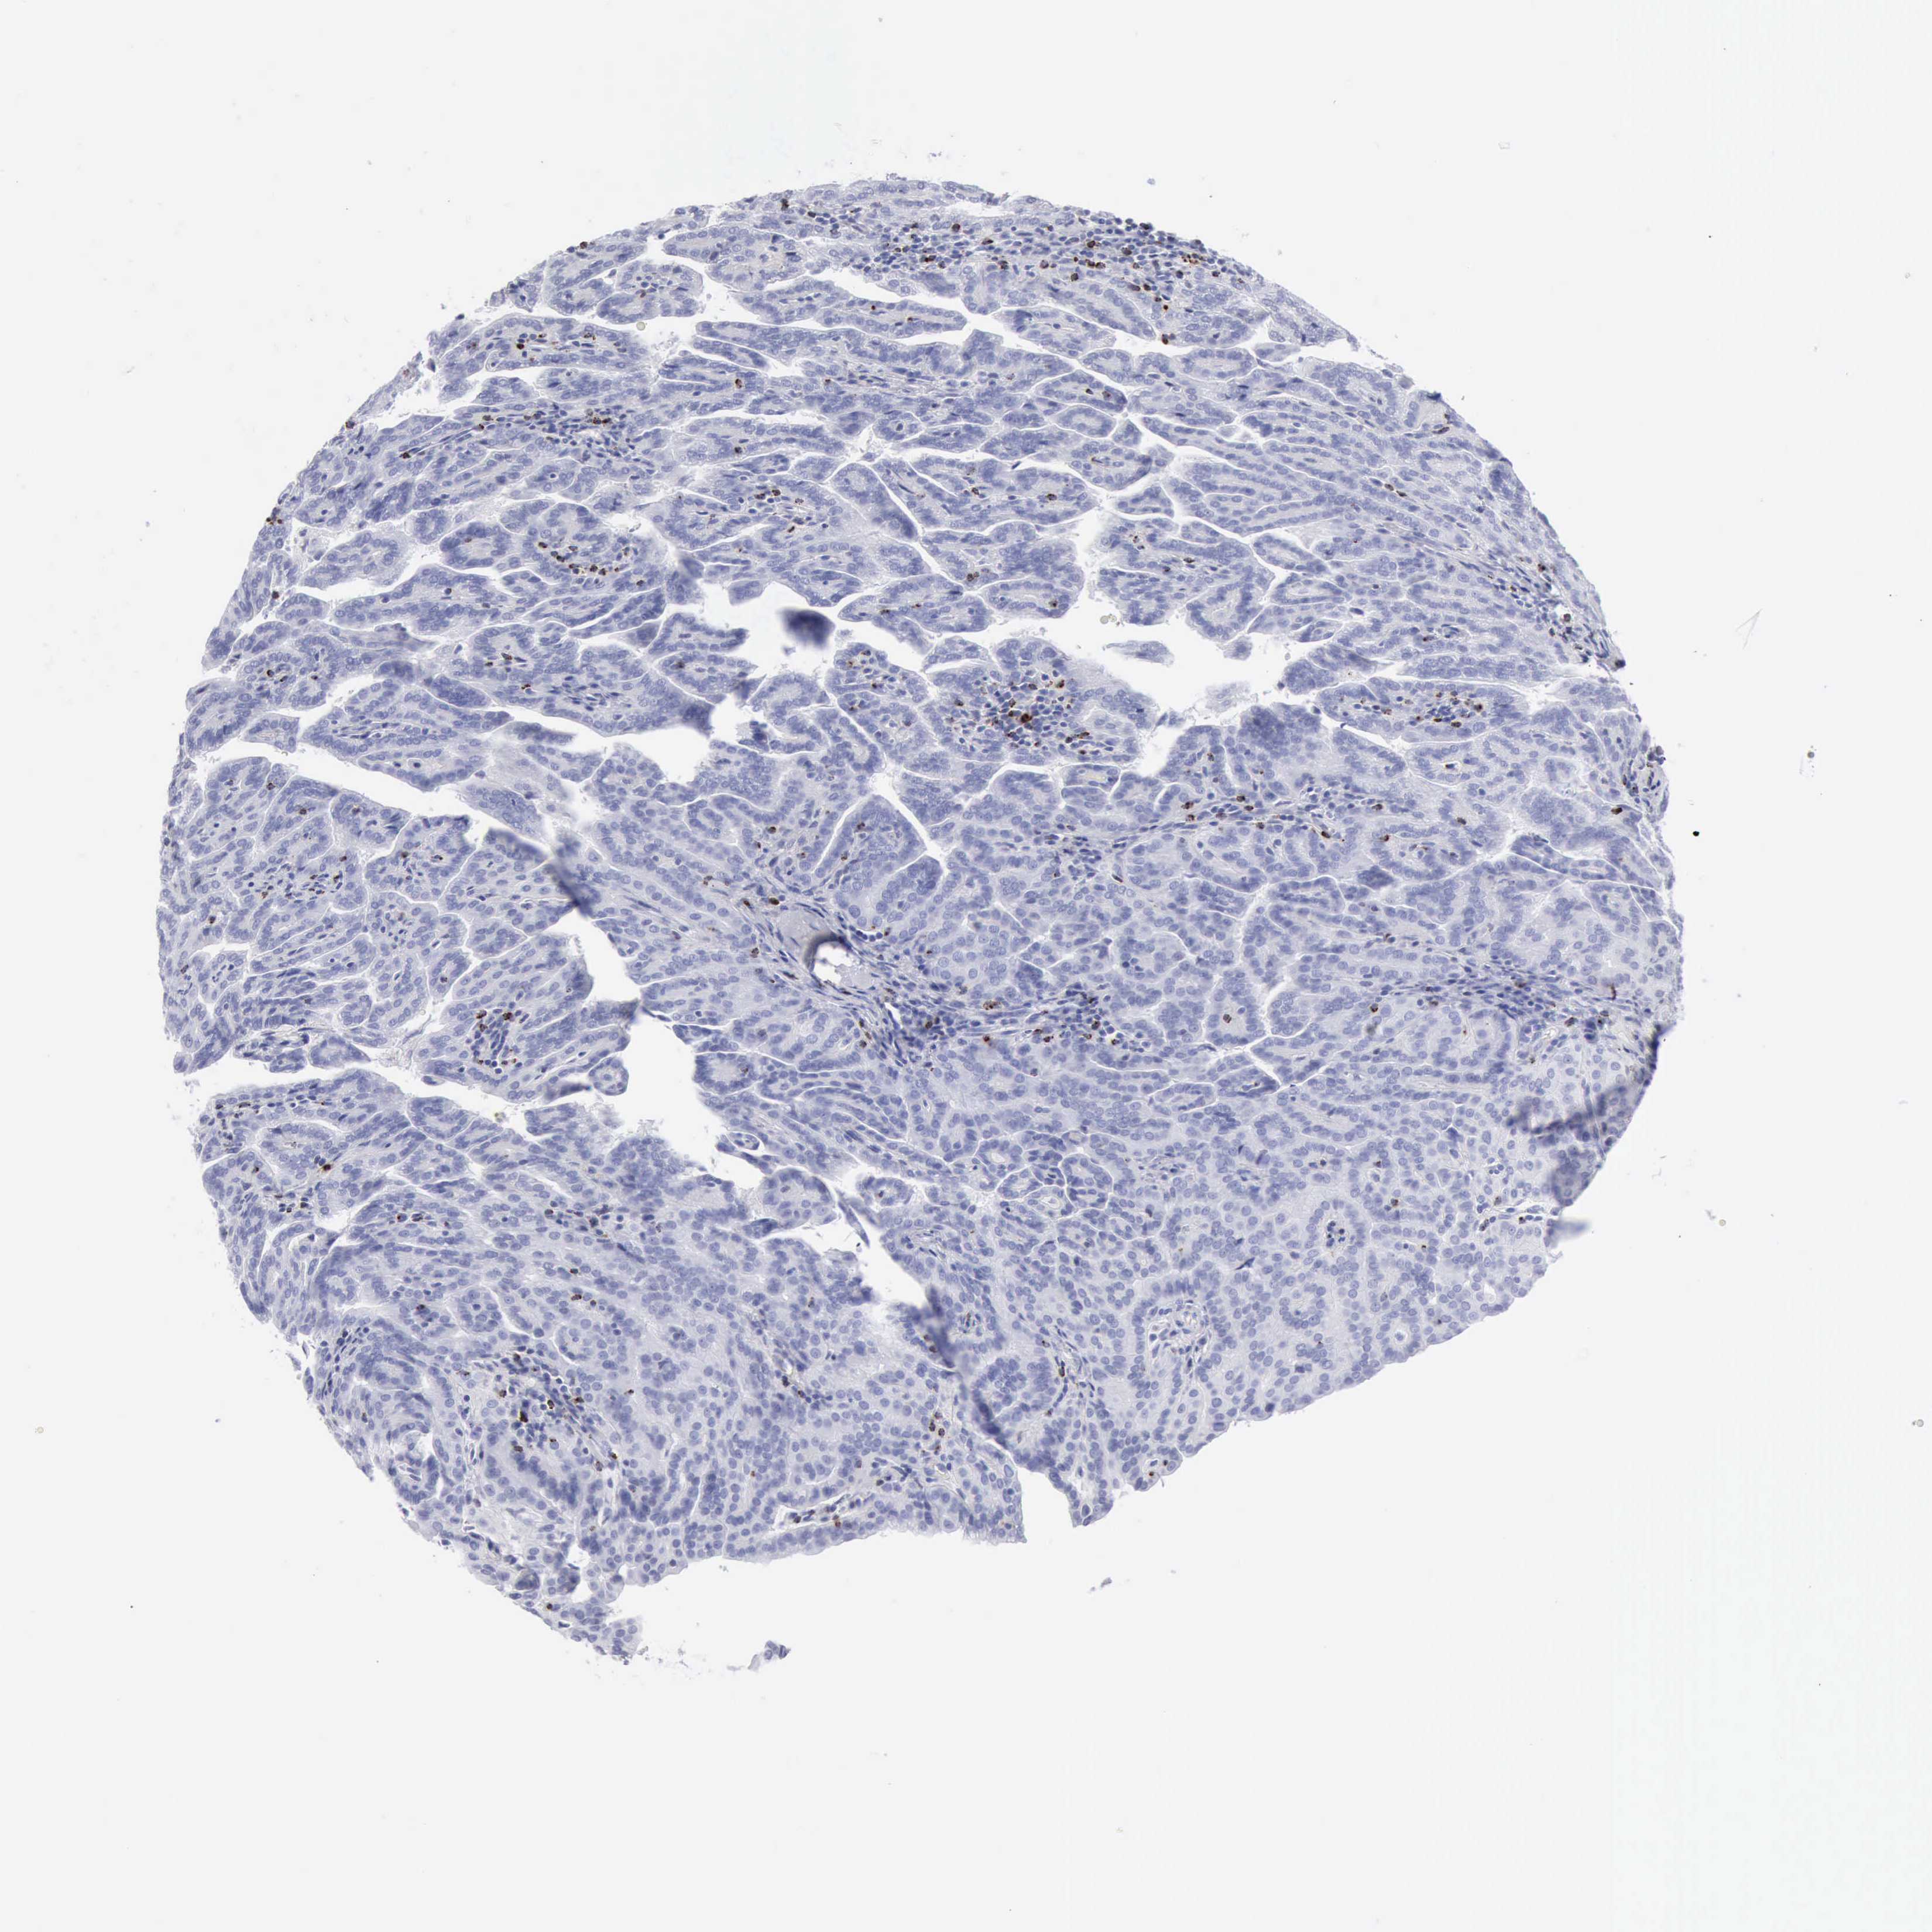

TCGA RNA samplesi

RNA-seq data is reported as average FPKM (number Fragments Per Kilobase of exon per Million reads), generated by the The Cancer Genome Atlas (TCGA) .

Normal distribution across the dataset is visualized with box plots, shown as median and 25th and 75th percentiles. Points are displayed as outliers if they are above or below 1.5 times the interquartile range. FPKM values of the individual samples are presented next to the box plot.

Average pTPM 11.5

Number of samples 100